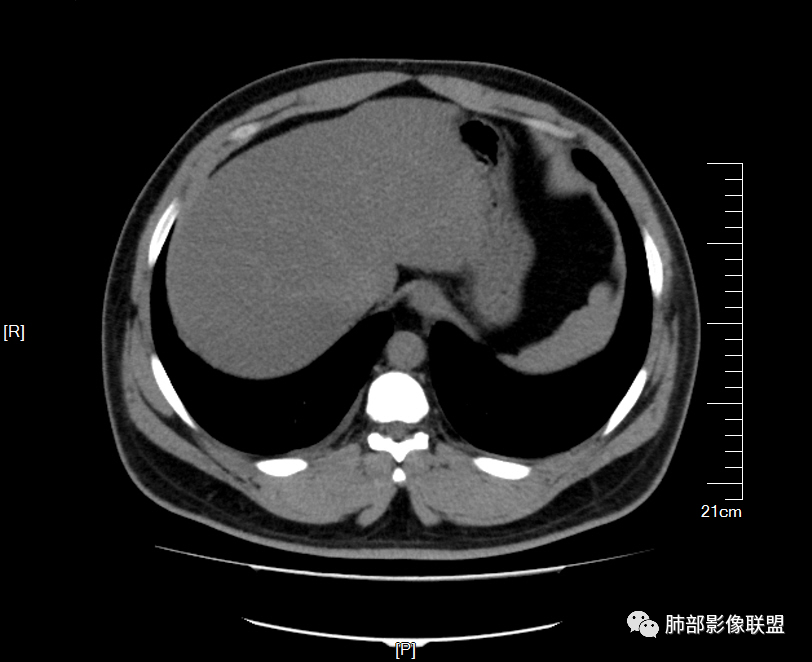

男32岁。既往曾发现血肌酐升高.此次因左足痛6天入院。有痛风、高血压病史。两肺弥漫性的病变,小片状或者结节状为主病变,小叶中心分部为主,边界不清。心影比较饱满,肝实质密度均匀的降低。考虑为肝损害的影像学改变。综合考虑多功能脏器的损害,肺部损害肺泡炎?肺水肿?或病毒性的肺炎?

少量积液,脂肪肝

@於雄 九江市一医院影像?肌酐高,估计一过性,不然不会轻描淡写,一带而过